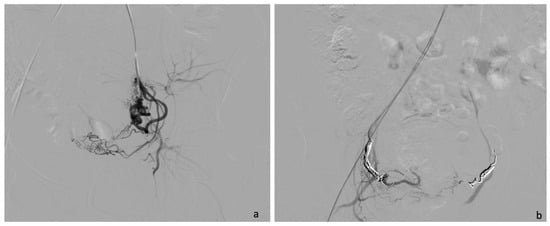

4.1.1. Case 1 (CSP Type I)

- Sorrentino, F.; De Feo, V.; Stabile, G.; Tinelli, R.; D’Alterio, M.N.; Ricci, G.; Angioni, S.; Nappi, L. Cesarean Scar Pregnancy Treated by Artery Embolization Combined with Diode Laser: A Novel Approach for a Rare Disease. Medicina 2021, 57, 411. [Google Scholar] [CrossRef]